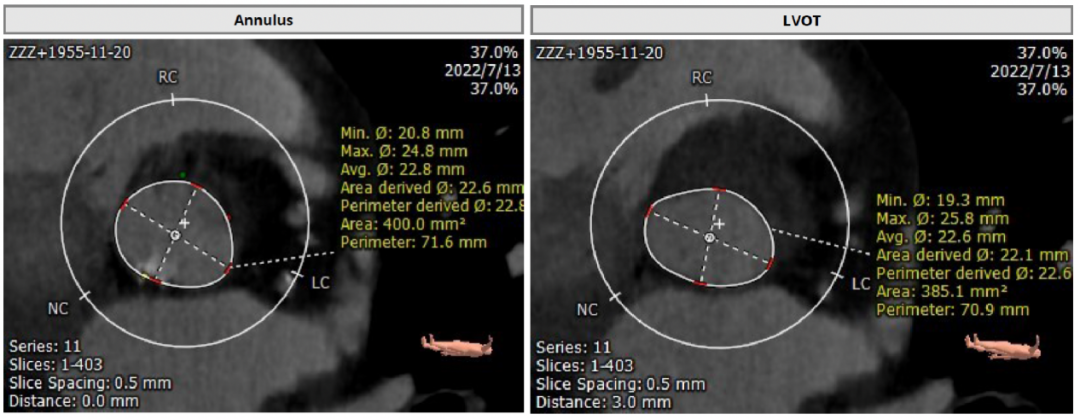

术前CT评估